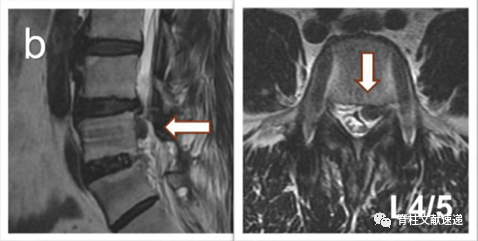

病例一:L5/S1椎间盘突出症,L4/5无症状椎间盘突出,行L5/S1固定融合术,3年后出现L4/5椎间盘突出症,行手术治疗,如下图,a为术前,b为术后。